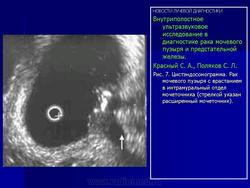

Эндовезикальное сканирование позволяет выявить распространение опухоли на интрамуральный отдел мочеточника (Рис.7) и предстательную железу (стадия Т4). Однако следует отметить, что при инвазии опухоли в предстательную железу более информативным является трансректальное сканирование. Что касается распространения опухоли на другие органы и ткани (брюшина, кости таза, тонкий кишечник и прямая кишка), то возможности эндовезикального исследования здесь ограничены. В подобных случаях значительную помощь в диагностике оказывает компьютерная томография. То же самое можно сказать и о диагностике метастатического поражения регионарных лимфатических узлов.